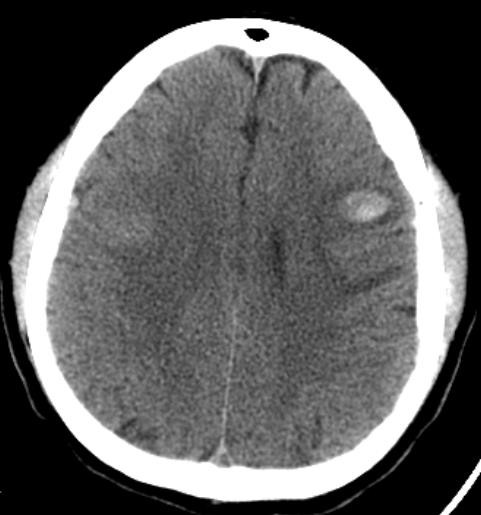

La angiotomografía cerebral evidencia la presencia de múltiples áreas hiperdensas de distribución difusa, bilateral que compromete ambos lóbulos frontales, compatibles con hemorragias intraparenquimatosas de focos múltiples, asociado a edema perilesional (Fig 1 y 2), además se identificó la presencia de signo del delta vacío secundario a trombosis venosa dural que compromete el seno sagital superior, con extensión a la confluencia de los senos, seno transverso derecho, así como el seno yugular y vena yugular ipsilateral (Fig 3 y 4).

Figura 1,2: Imágenes de angiotomografía cerebral en proyección axial y sagital, en ventana de cerebro que muestra la presencia de múltiples áreas hiperdensas en lóbulos frontales, de distribución difusa, bilateral.